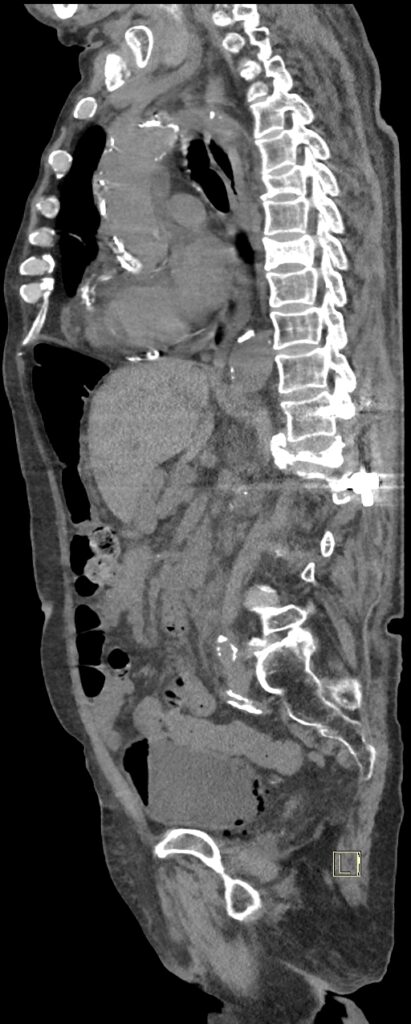

Figurile 3 şi 4: sagital examinare CT abdomen şi pelvis fără substanță de contrast

Discuţie caz nr 131: pacient de 85 de ani cunoscut diabetic este adus la camera de gardă pentru dureri abdominale difuze, efectueaza CT fără substanță de contrast deoarece eGFR este 21 mL/min/1.73 m². Se evidențiază pericardita în cantitate medie, mai multe chiste renale – unul spontan hiperdens, multiple plăci aterotrombotice calcificate la nivelul aortei și ramurilor precum și multiple bule aerice în peretele vezicii urinare și conținut hidro-aeric al vezicii urinare. Ultimele două elemente sugerează diagnosticul de cistita emfizematoasă.